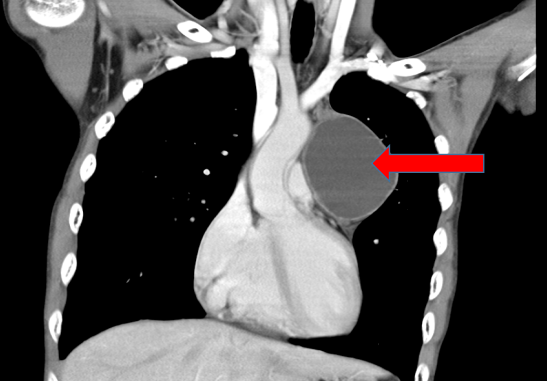

这名19岁少年是刚入学的大一新生,在学校组织体检中,胸透检查提示“前纵膈区域异常密度影”,随后至佛山市第一人民医院胸外科进一步检查。经胸部增强CT详细评估,医生发现其前纵膈位置存在一个大小约10cm的占位性病变,肿瘤内部可见脂肪密度影与钙化灶,结合肿瘤标志物(AFP、β-HCG)检测结果正常,初步诊断为“良性前纵膈畸胎瘤”。

尽管肿瘤性质偏向良性,但因其位置靠近心脏大血管,且体积已超过临床建议手术的3厘米阈值,若继续拖延,可能出现肿瘤压迫气管、食管引发呼吸困难、吞咽困难,甚至肿瘤破裂导致急性胸膜炎等风险。胸外科团队经过多学科会诊,考虑肿瘤较大,最终决定为其采正中开胸手术,在保证手术安全的同时,完整切除肿瘤。

最常用的是胸部 CT,能清晰看到肿瘤的位置、大小,还能通过 “特殊信号” 初步判断 —— 比如看到 “黑色的脂肪影”“白色的钙化点(可能是牙齿 / 骨骼)”,大概率就是畸胎瘤。胸片可初步筛查,但细节看不清;MRI 则能进一步看肿瘤是否侵犯心脏、大血管,帮医生制定手术方案。